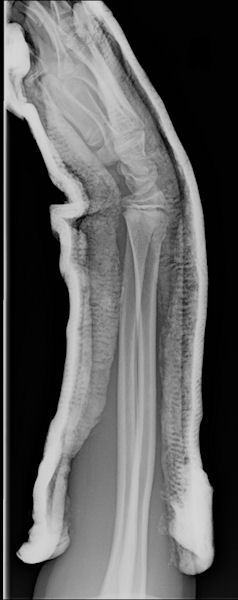

Kryštof a jeho zlomená ruka.